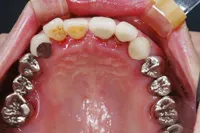

金属を白くし、歯茎の黒ズミを改善したケース

■治療前

■治療後

| 主訴 | 全体的に白い歯にして見た目をきれいにしたい 歯茎が黒くなっているのが気になる、歯ならびも良くしたい |

| 治療方法 | 矯正治療+歯茎の黒ずみの改善+補綴治療 |

| 治療期間 | 3年 |

| 通院回数等 | 約40回 |

| 費用 | 約350万円 |

| リスク・副作用 | 矯正治療も行ったので治療期間が長くなった |